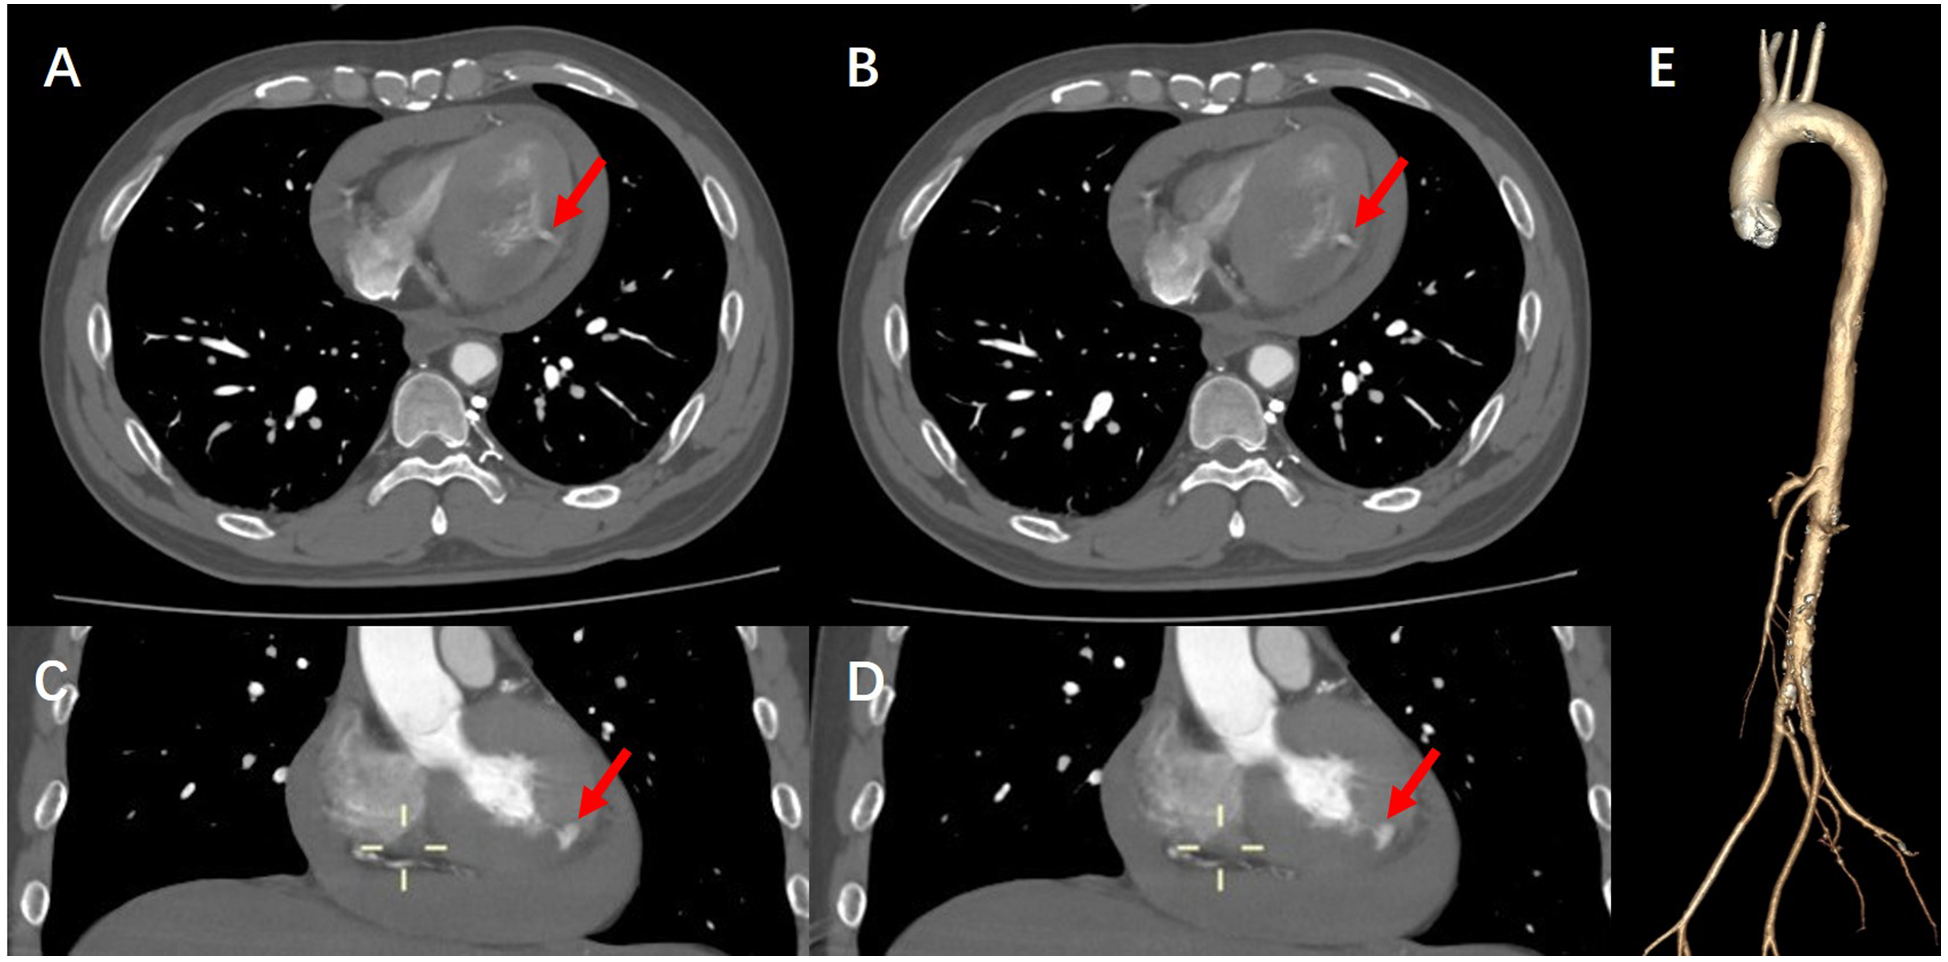

During this period, although the patient underwent echocardiography, the bedside ultrasound did not find pericardial tamponade, but only moderate amount of pericardial effusion due to the patient's obesity, restlessness and the limitations of the ultrasound operator's level. Subsequent aortic CTA revealed a significant volume of pericardial effusion without evidence of aortic dissection. The clinical manifestations were initially attributed to the combined effects of pericardial effusion and coronary pathology. To further clarify the cause of death, a senior radiologist meticulously reviewed the imaging studies and identified contrast medium extravasation from the myocardium into the pericardial cavity (Figure 3). After aortic dissection was ruled out, the patient was returned to the cath lab for further treatment of distal circumflex branch occlusion and pericardiocentesis. Procedure: The guide wire was sent through the catheter and passed through the distal end of the circumflex branch occlusion segment successfully. Blood flow passed through the circumflex branch occlusion segment after balloon expansion. The TIMI grade was 3 (Figure 2B). Unfortunately, pericardiocentesis under DSA guidance was not successful.

Figure 3

(A,B) CTA of the aorta demonstrate contrast extravasation into the myocardium, along with right-sided heart failure and pericardial effusion. (C,D) Coronal views of aortic CTA further reveal contrast leakage into the myocardial tissue. (E) Three-dimensional reconstruction of the aorta confirms the absence of aortic dissection, intramural hematoma, or other vascular anomalies.

Early diagnosis and timely emergency surgical treatment of such patients can be expected to be successful. Given its convenience and rapid availability, echocardiography remains recognized as the first-line diagnostic modality for cardiac rupture (11, 12). Although echocardiography demonstrates moderate sensitivity (70%) and high specificity (90%) in detecting cardiac rupture, its diagnostic accuracy heavily depends on operator expertise and patient cooperation (13), which can be particularly challenging in critically ill patients. Therefore, when echocardiography fails to provide a definitive diagnosis, supplementary imaging modalities should be considered. In our case, no extravasation of contrast media was found in the patient during coronary angiography, but the clinical manifestations were inconsistent with coronary vascular disease. However, in order to rule out aortic dissection, we performed an aortic CTA examination and observed contrast agent shuttling through the myocardium and reaching the pericardium, definitively diagnosing the patient's heart rupture diagnosis.